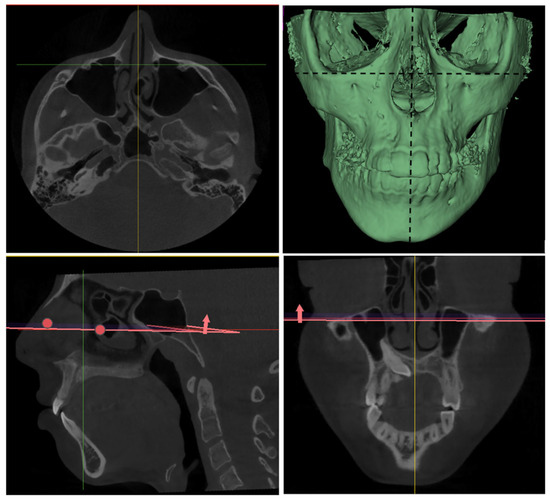

Three-Dimensional Evaluation of TMJ Morphology in Individuals with Maxillary or Mandibular Impacted Canines: A CBCT-Based Retrospective Study

Background/Objectives: This study aimed to evaluate temporomandibular joint (TMJ) morphology in individuals with impacted maxillary and mandibular canine teeth using cone beam computed tomography (CBCT) and to compare the findings with those of a control group without impacted canines. Methods: A total [...] Read more.

Background/Objectives: This study aimed to evaluate temporomandibular joint (TMJ) morphology in individuals with impacted maxillary and mandibular canine teeth using cone beam computed tomography (CBCT) and to compare the findings with those of a control group without impacted canines. Methods: A total of 80 individuals were included in this retrospective study. Based on CBCT images, participants were divided into three groups: the impacted maxillary canine group (n = 30), impacted mandibular canine group (n = 20), and control group (n = 30). CBCT images were oriented in the 3D Slicer software according to the Frankfurt Horizontal plane and the midsagittal reference line. Condylar width, length, position, angular parameters, joint spaces, and condylar volume were measured. Appropriate parametric and non-parametric statistical tests were used for intergroup comparisons. Results: The control group exhibited significantly higher values of condylar width, coronal condylar position and angle, certain joint spaces, and condylar volume compared with both impacted maxillary and mandibular canine groups (p < 0.05). In particular, significant differences were observed for condylar width (p ≤ 0.002) (Control: 19.76 ± 2.09 mm, Maxillary: 17.92 ± 2.14 mm, Mandibular: 17.76 ± 1.64 mm), coronal condylar position (p < 0.001) (Control: 7.50 ± 1.34 mm, Maxillary: 6.02 ± 0.89 mm, Mandibular: 6.30 ± 0.83 mm), coronal condylar angle (p < 0.001) (Control: 25.09° ± 4.40, Maxillary: 28.80° ± 3.70, Mandibular: 33.37° ± 4.10), and condylar volume (p < 0.001) (Control: 1755.87 ± 357.32 mm3, Maxillary: 1337.18 ± 302.65 mm3, Mandibular: 1252.71 ± 369.24 mm3). No significant differences were found between the impacted maxillary and mandibular canine groups for most parameters (p > 0.05). Right–left side comparisons demonstrated that bilateral symmetry was largely preserved, except for condylar volume (p > 0.05). Conclusions: The presence of impacted canines may influence TMJ morphology, particularly at the level of condylar morphometry and joint spaces. Therefore, considering TMJ morphology in addition to local dental factors when evaluating impacted canines may provide a more comprehensive approach to orthodontic diagnosis and treatment planning. Full article

(This article belongs to the Section Medical Imaging and Theranostics)

Show Figures

Figure 1